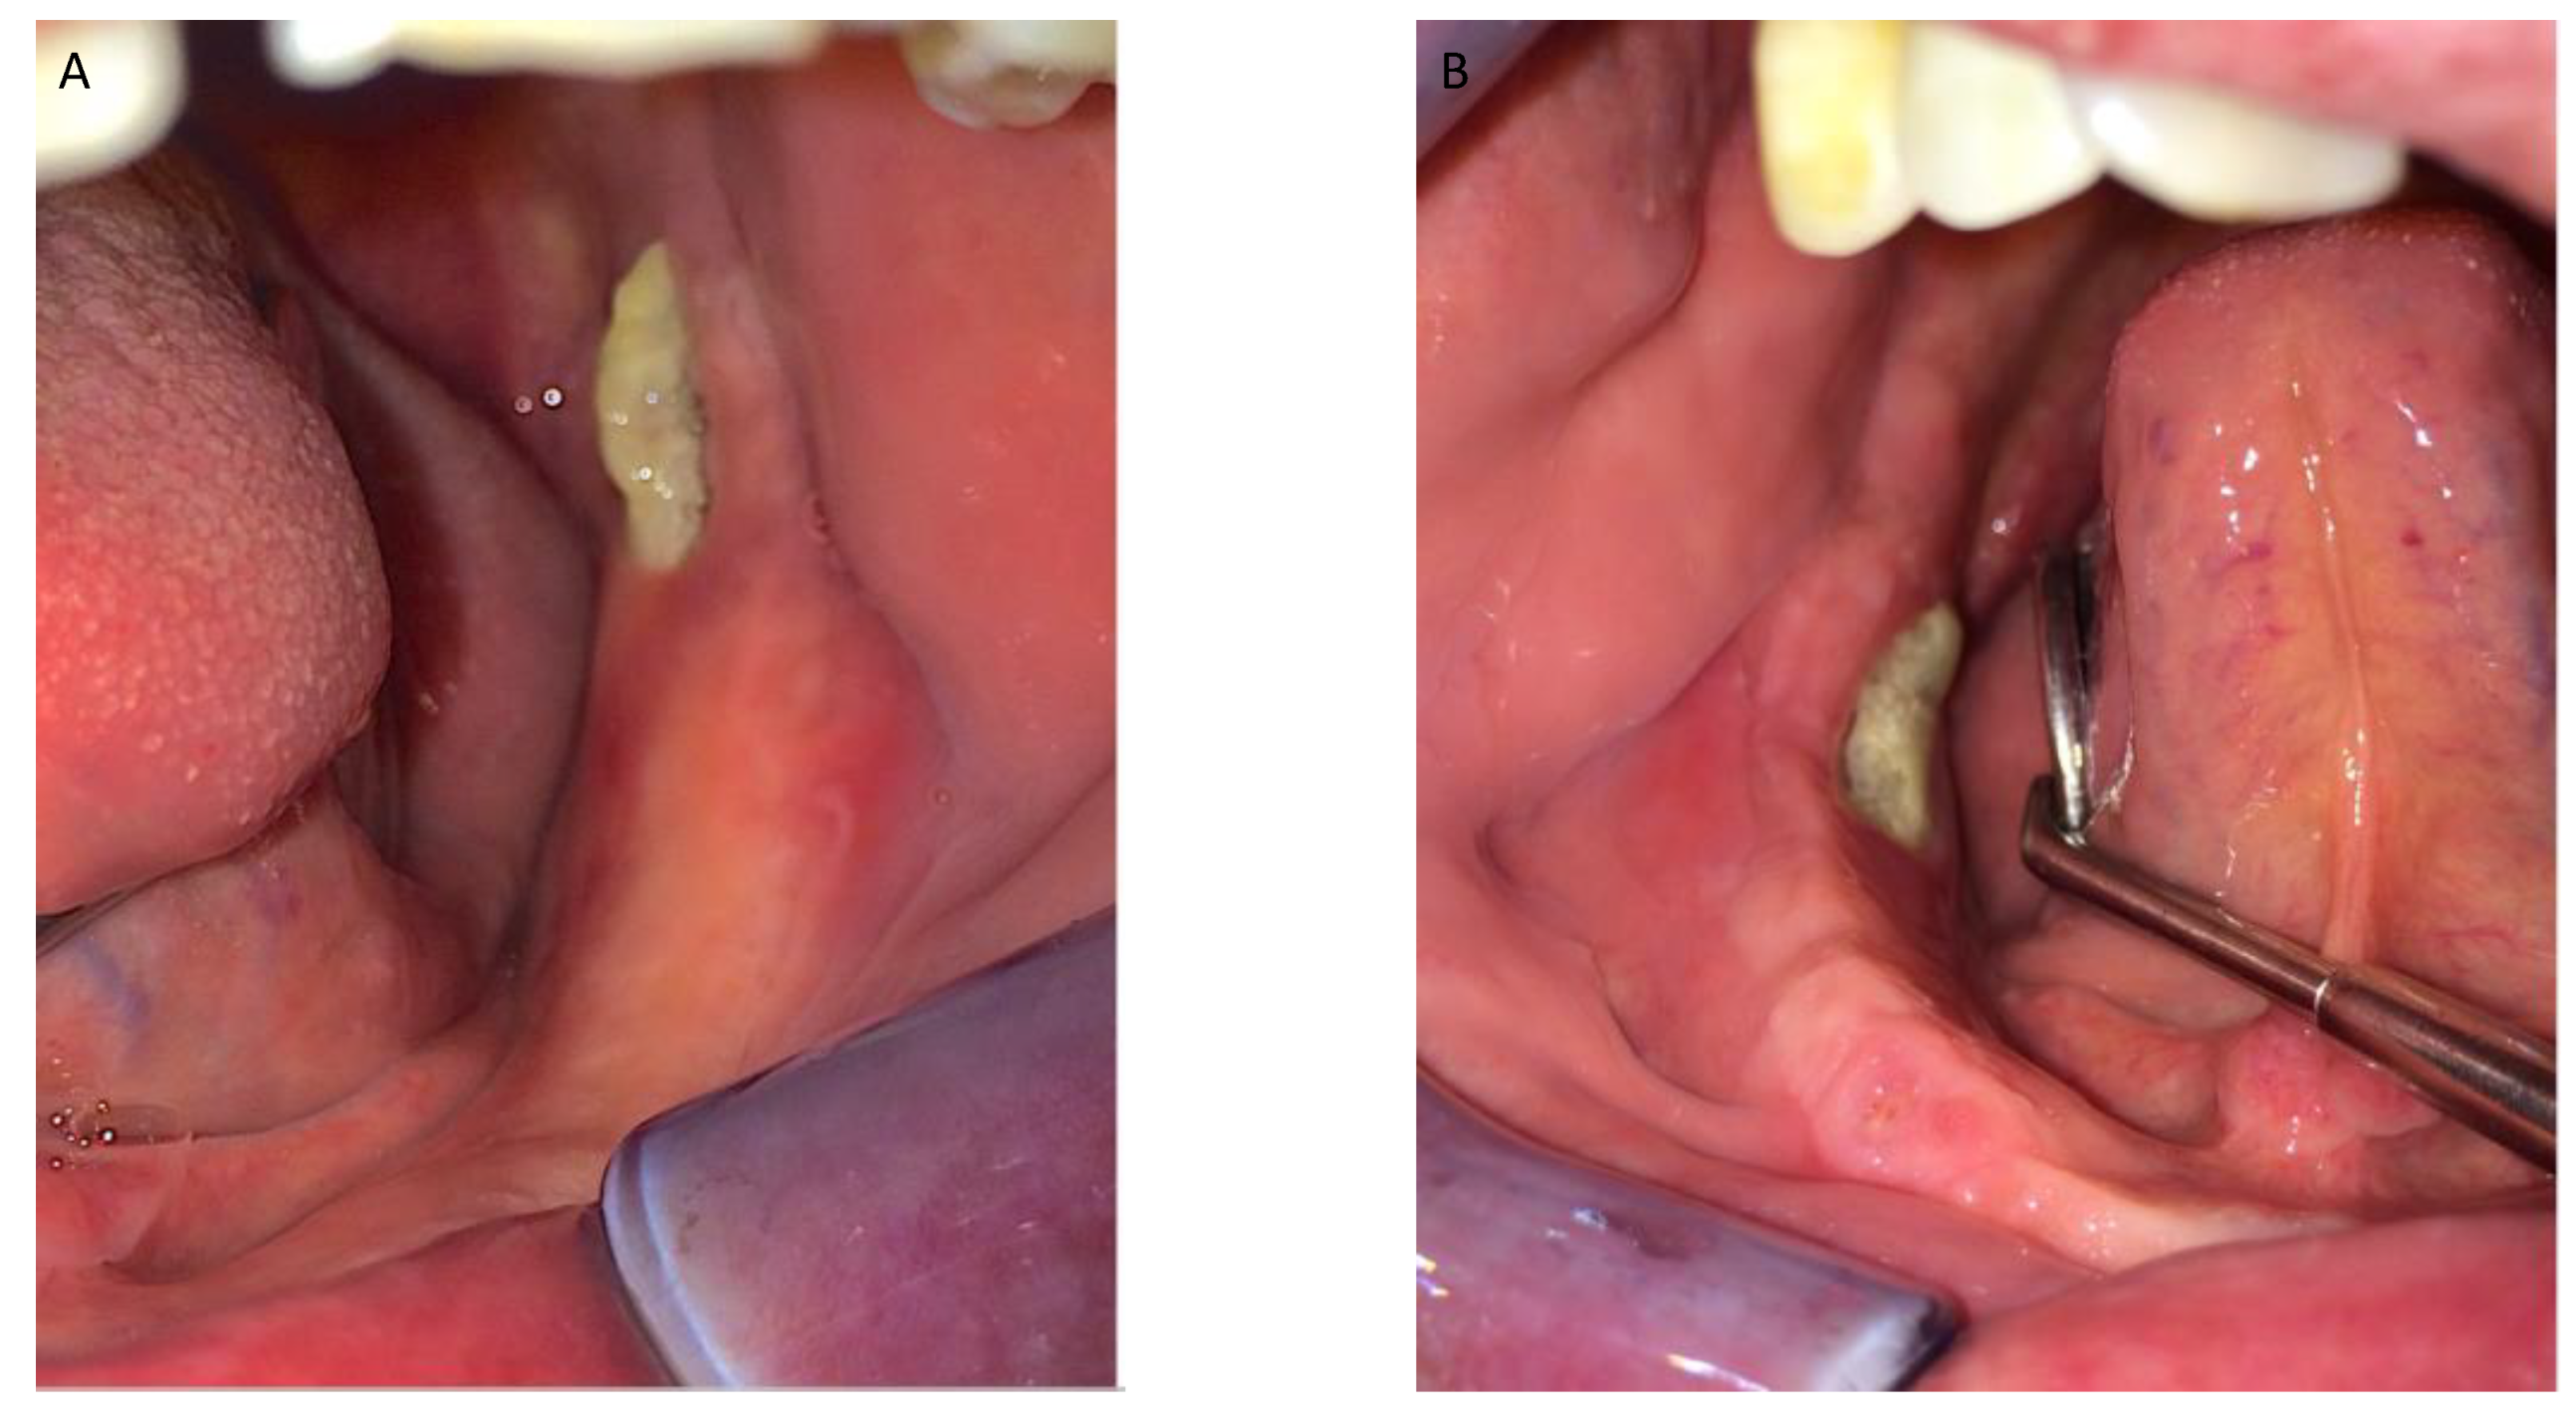

Figure 1, Figure 2, Figure 3, Figure 4, Figure 5, Figure 6 and Figure 7 show the progress of treatment in one of the patients of the test group. In Figure 3 reduction of the medullar space is visible, that may create a chronic ischemic area susceptible to necrosis.

Figure 1.

Pre-operative intra-oral view from a MRONJ patient with bilateral defect. (A) left side; (B) right side.